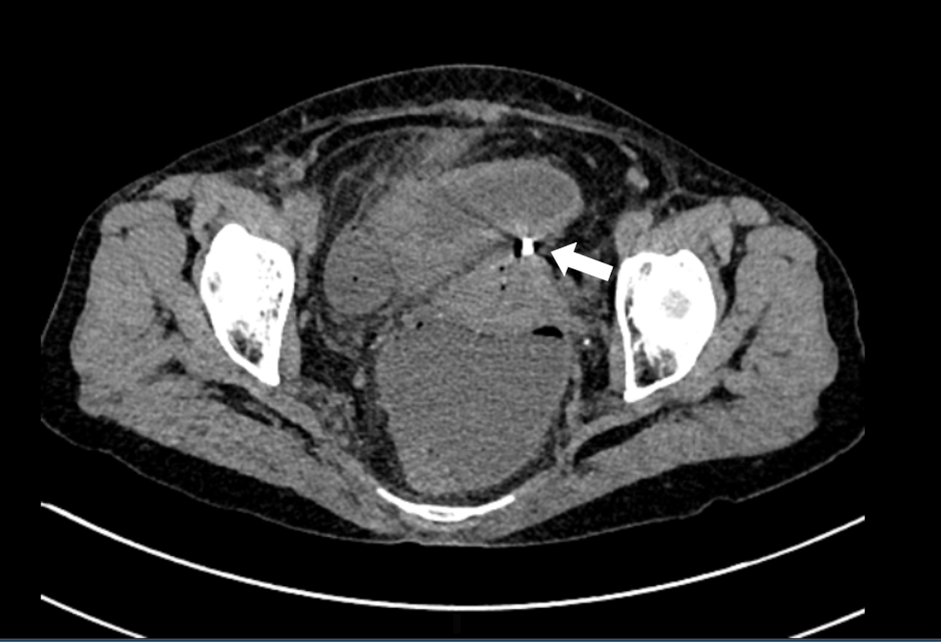

Dụng cụ tử cung xuyên qua thành tử cung vào ruột (mũi tên trắng). Ảnh: BVCC

Siêu âm ổ bụng cho thấy các quai ruột ứ đọng dịch, giảm nhu động, ít dịch tự do ổ bụng. Chụp cắt lớp vi tính thấy hình ảnh dịch khí tự do trong ổ bụng, tắc ruột cơ năng, dày thành ruột vị trí hố chậu phải và dị vật xuyên thủng đáy tử cung.